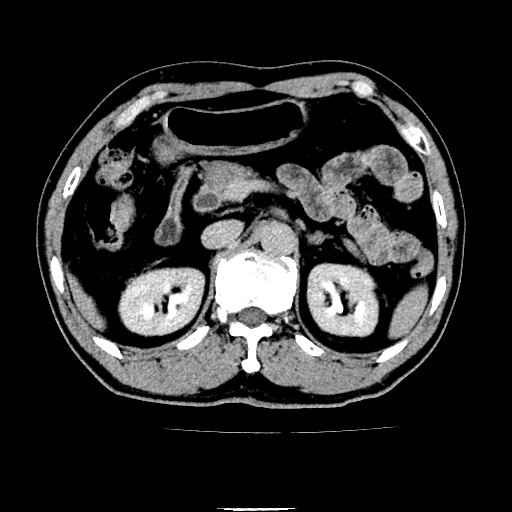

以下是引用chenqiong在2010-3-25 20:56:00的发言:[br]1、胆囊炎,胆囊息肉[br]2、肝内胆管及胆总管扩张,胆总管下端结石[br]3、十二指肠乳头旁憩室

以下是引用zxl51642在2010-3-26 10:47:00的发言:[br]胆囊炎,胆囊息肉,胆总管扩张,但未看到明显肿块,肝内胆管扩张不像恶性,炎性狭窄或阴性结石可能吧,建议mrcp,右肾小囊肿